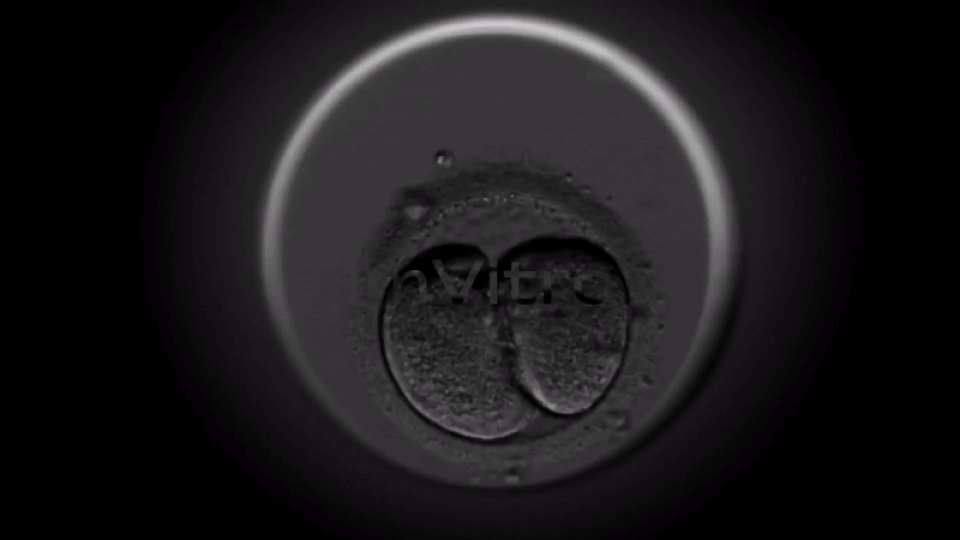

With its Embryoly platform, this is exactly the need ImVitro is looking to fulfill. Speaking to Tech.eu in an exclusive interview, ImVitro founder Dr. Alexandra Boussommier explained that the company’s SaaS platform combines the power of cell culture and AI to bring automation to the IVF fertility imaging process, thereby saving clinicians’ valuable time, eliminating a number of human errors and delivering reliable predictions to embryologists at scale. And not least to mention, providing patients with an increased and improved layer of transparency to the entire process.

Uploading videos from already-existing microscope technology within clinics’ labs, Embryoly analyses these videos against a database of more than 35 million data points, addressing more than 30 clinical factors, resulting in a hybrid score that includes the patient's BMI, uterus receptivity, and spermatozoa mobility.

This not only dramatically reduces the time clinicians spend on searching for key biological events in embryonic development, but also provides predictions based on the synergies between the patient’s medical profile and the development of the embryo as early as day 3 without the need for embryologists to annotate as they do today.